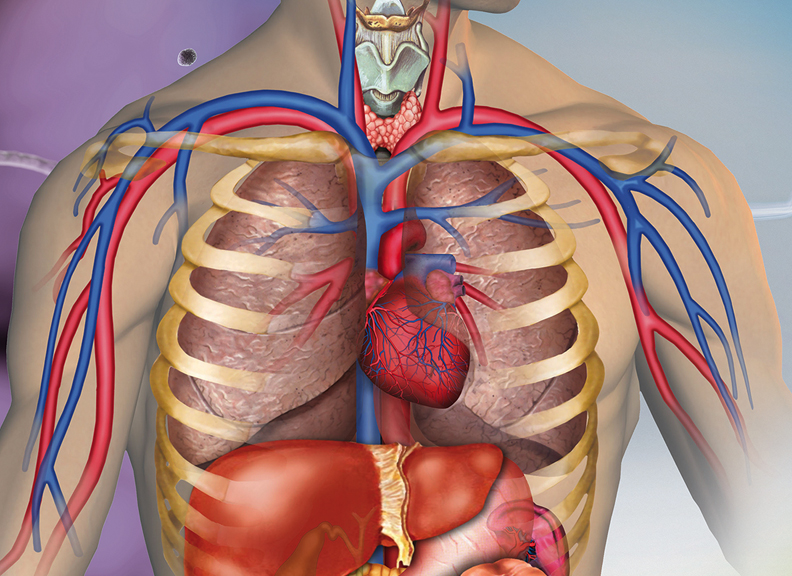

Изображения и визуализация внутренних органов человека